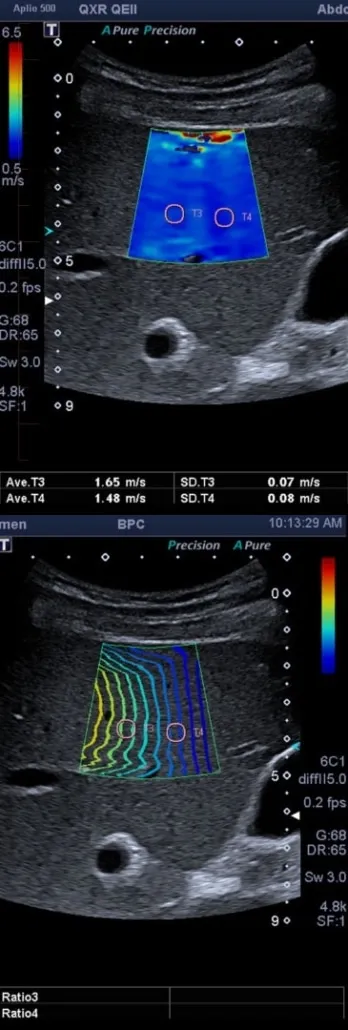

Élastographie hépatique — Évaluation de la fibrose hépatique

L’élastographie hépatique est l’imagerie de la fibrose hépatique en utilisant les ondes de cisaillement pour une analyse reproductible et non invasive.

Les techniques échographiques récentes permettent d’évaluer la fibrose hépatique de façon non invasive et non douloureuse. Cela permet de suivre les atteintes chroniques hépatiques, notamment les hépatites et les stéatoses chroniques (foie gras).

La fibrose hépatique apparaît quand du tissu cicatriciel s’accumule au sein du parenchyme hépatique sain. Lorsque ce tissu fibreux s’accumule chroniquement et supplante une grande partie du tissu sain, on parle de cirrhose hépatique.

Nos machines utilisent les ondes de cisaillement pour mesurer cette fibrose de façon non invasive, quantifiée très précisément et de façon reproductible. Contrairement aux autres techniques d’élastographie ultrasonore, les ondes de cisaillement permettent une mesure dont la précision et la reproductibilité sont indépendantes de l’opérateur.